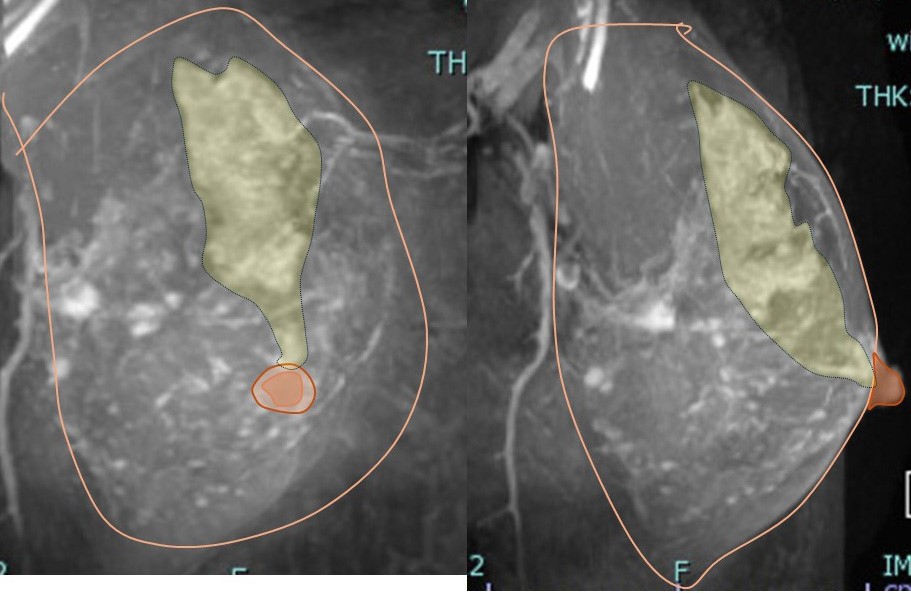

3. 病変に対する(マージンをつけた)切除範囲

乳頭を超えた切除としていますが、乳頭は皮膚を含めて切除しません。

♯側面で見るとよくわかります。